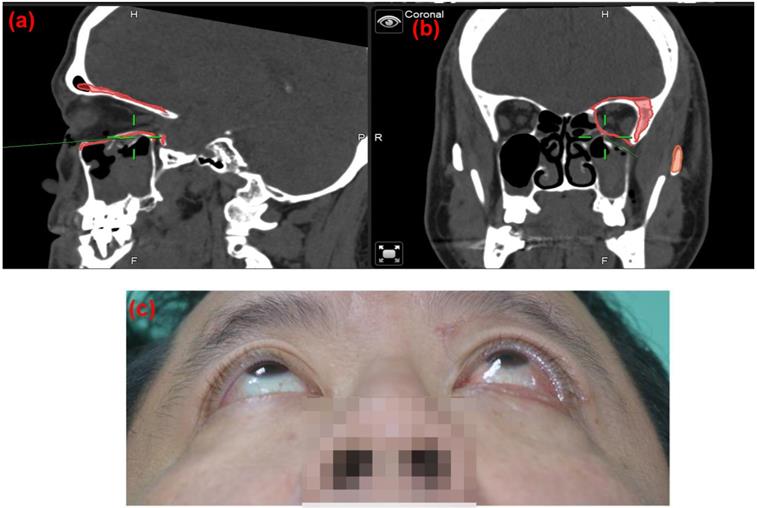

Figure 6

Post-operation 8 weeks follow up CT images based on the 3D reconstruction of the orbital cavity by Brainlab® software of Case 10 (Rt side Zygomatic complex fracture). (a) Rt side orbital volume: 25.035 cm3, (b) Lt side orbital volume: 24.957 cm3 Difference: 0.078 cm3 (c) sagittal view. ABCcolla® Collagen Bone graft was implanted (d) post-operation 2 months follow-up. Without any complaint was noted.

Figure 5

Case 9, 49 y/o male patients, left side orbital floor blowout fracture, Left eye post-op one month, Hertel OD 18mm, OS 21mm,( Left eye exophthalmos 3mm). The navigator assisted surgery allows the surgeon to go into the deep space (green line) which is close to the optic nerve without compromising the optic nerve function.